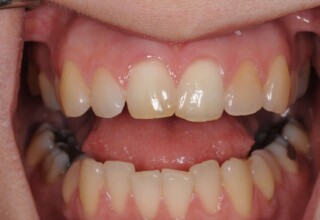

Αποκατάσταση διαστημάτων μεταξύ κεντρικών και πλαγίων τομέων

Τα διαστήματα έχουν δημιουργηθεί κυρίως λόγω των στενών πλαγίων. Μετά την ολοκλήρωση της ορθοδοντικής θεραπείας τα διαστήματα “έκλεισαν” με την τοποθέτηση δύο αποκαταστάσεων σύνθετης ρητίνης.